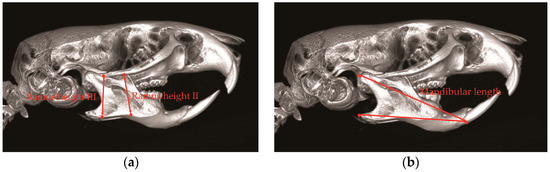

- Tsai, C.Y.; Huang, R.Y.; Lee, C.M.; Hsiao, W.T.; Yang, L.Y. Morphologic and bony structural changes in the mandible after a unilateral injection of botulinum neurotoxin in adult rats. J. Oral Maxillofac. Surg. 2010, 68, 1081–1087. [Google Scholar] [CrossRef] [PubMed]

- Tsai, C.Y.; Shyr, Y.M.; Chiu, W.C.; Lee, C.M. Bone changes in the mandible following botulinum neurotoxin injections. Eur. J. Orthod. 2010, 33, 132–138. [Google Scholar] [CrossRef] [PubMed]